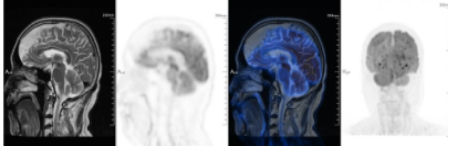

PET-CT复查结果显示,原双侧腋窝淋巴结显示不清;原C7、双侧肱骨、多个胸椎、胸骨、多处肋骨、多个腰椎、骨盆骨、左股骨上段骨质破坏已不明显,PET示代谢较前明显降低(Deauville 3分);原回肠肠壁增厚已不明显;原左臀及左大腿根部骨骼肌肉内多发结节异常放射性浓缩影已不明显,疗效评估达到CR。

上. 基线PET-CT;

下. 塞利尼索联合地西他滨和R-Gemoxd 2疗程后PET-CT